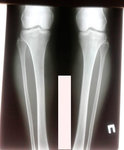

Пациентка - 37 лет.

Дата операции - 24.10.2019г.

Диагноз: варусная деформация голеней. Ротация с обеих сторон.